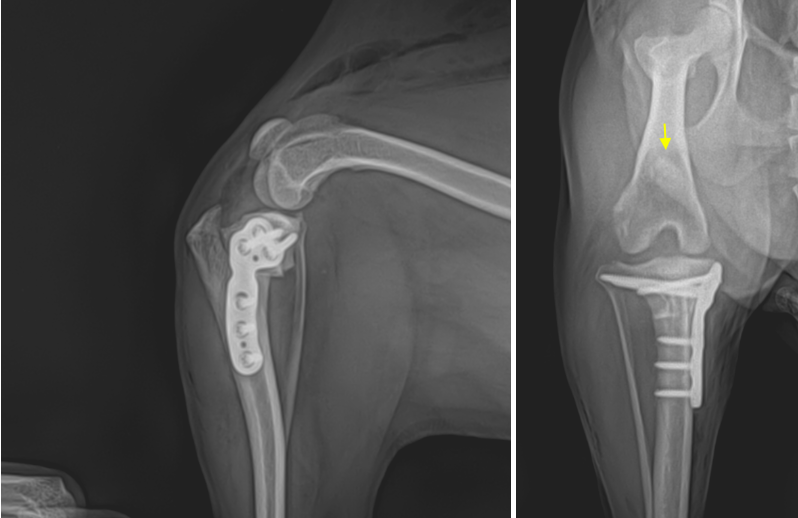

십자인대 TPLO 수술 결과

환자는 약 50분의 슬개골 탈구 & TPLO 수술을 마치고 안정적으로 회복하였습니다. 수술은 수술 전 TPA 계획에 따라 잘 진행되었으며, X-ray 에서도 플레이트와 스크류들이 잘 장착되어있는 것이 확인됩니다.

강아지 TPLO 수술 후 방사선 사진 / 출처: 에스동물메디컬센터 양산점